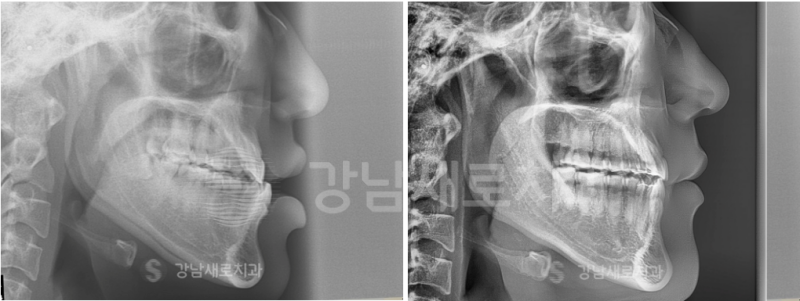

왼쪽 사진은 소구치를 뽑아낸 후

촬영한 사진이고, 오른쪽 사진은

이를 뽑은 부위로 앞에 위치한 치아를

이동시킨 후에 촬영된 모습이었는데요.

안쪽에 위치한 어금니들을 기준으로

앞니를 뒤쪽으로 이동시킨 것이었어요.

따라서 어금니의 위치나

교합(맞물림)에 눈에 띄게 큰 변화는

생기지 않았는걸 알 수 있었어요.